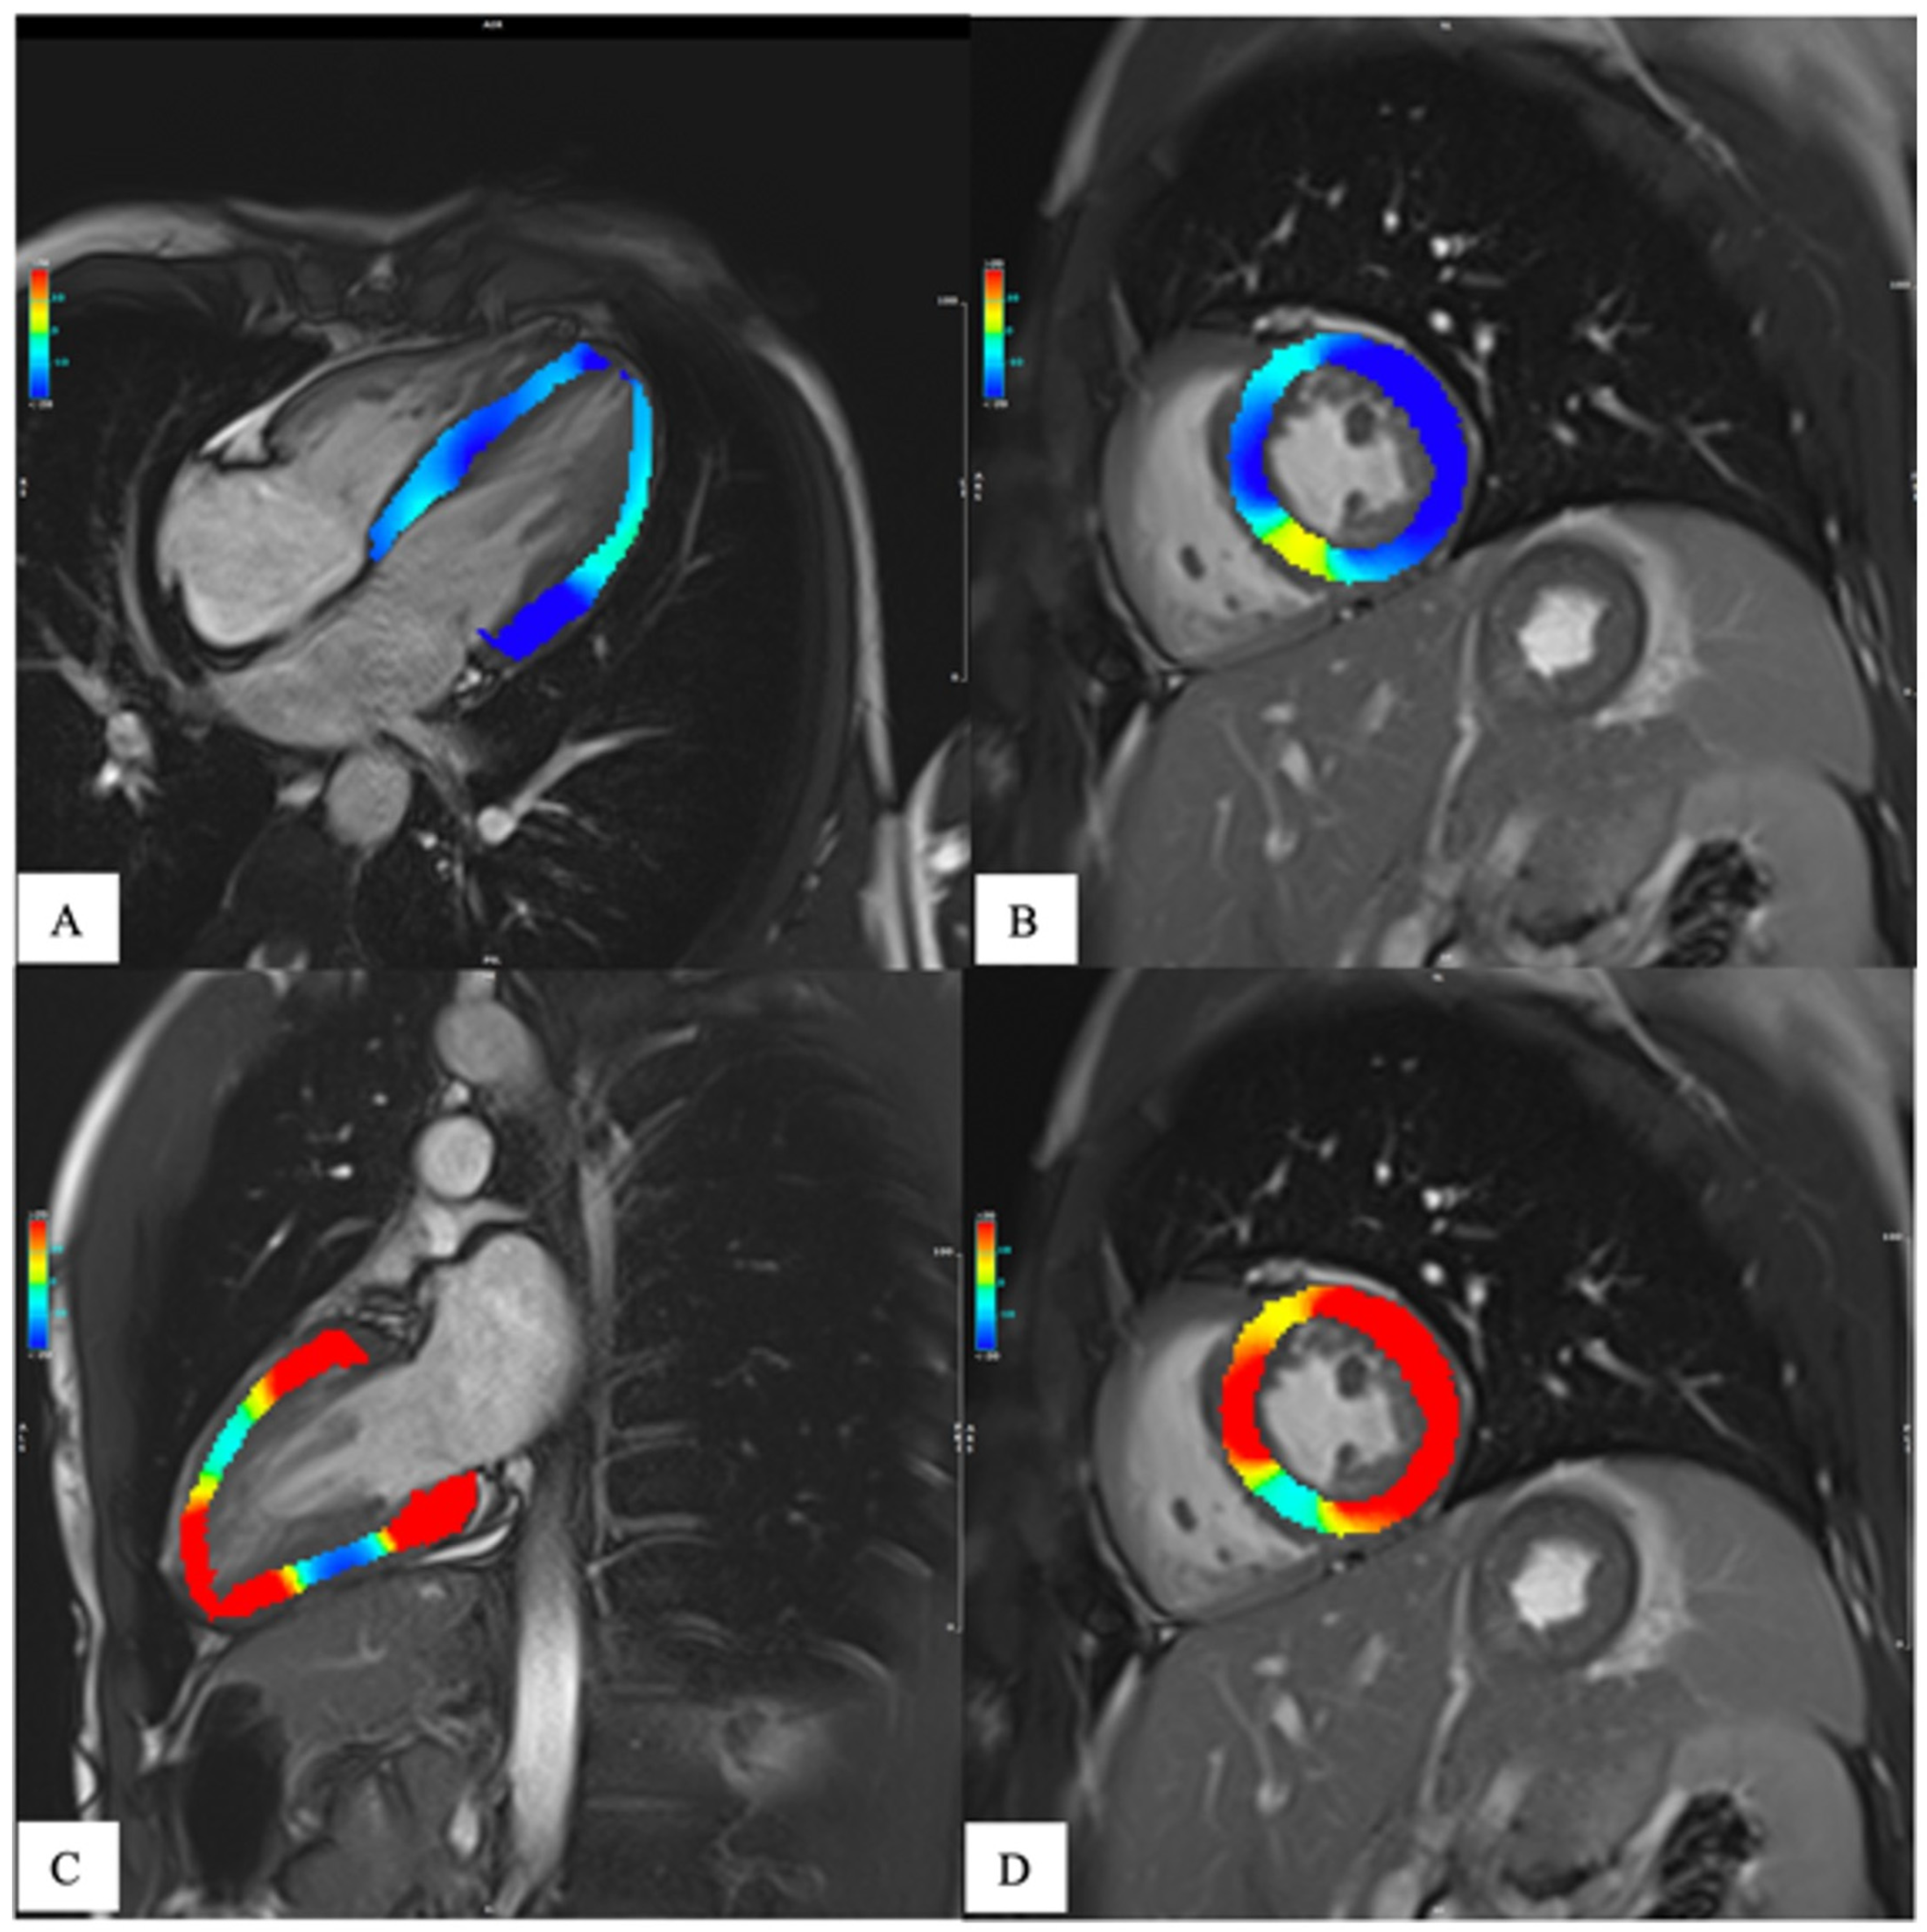

1.2. Magnetic Resonance

- Messroghli, D.R.; Moon, J.C.; Ferreira, V.M.; Grosse-Wortmann, L.; He, T.; Kellman, P.; Mascherbauer, J.; Nezafat, R.; Salerno, M.; Schelbert, E.B.; et al. Clinical recommendations for cardiovascular magnetic resonance mapping of T1, T2, T2* and extracellular volume: A consensus statement by the Society for Cardiovascular Magnetic Resonance (SCMR) endorsed by the European Association for Cardiovascular Imaging (EACVI). J. Cardiovasc. Magn. Reson. 2017, 19, 75. [Google Scholar] [CrossRef]

- Meloni, A.; Gargani, L.; Bruni, C.; Cavallaro, C.; Gobbo, M.; D’Agostino, A.; D’Angelo, G.; Martini, N.; Grigioni, F.; Sinagra, G.; et al. Additional value of T1 and T2 mapping techniques for early detection of myocardial involvement in scleroderma. Int. J. Cardiol. 2023, 376, 139–146. [Google Scholar] [CrossRef]

- Meloni, A.; Pistoia, L.; Positano, V.; Martini, N.; Borrello, R.L.; Sbragi, S.; Spasiano, A.; Casini, T.; Bitti, P.P.; Putti, M.C.; et al. Myocardial tissue characterization by segmental T2 mapping in thalassaemia major: Detecting inflammation beyond iron. Eur. Heart J.-Cardiovasc. Imaging 2023. [Google Scholar] [CrossRef]

- Meloni, A.; Positano, V.; Ruffo, G.B.; Spasiano, A.; D’Ascola, D.G.; Peluso, A.; Keilberg, P.; Restaino, G.; Valeri, G.; Renne, S.; et al. Improvement of heart iron with preserved patterns of iron store by CMR-guided chelation therapy. Eur. Heart J.-Cardiovasc. Imaging 2015, 16, 325–334. [Google Scholar] [CrossRef]

- Meloni, A.; Martini, N.; Positano, V.; D’Angelo, G.; Barison, A.; Todiere, G.; Grigoratos, C.; Barra, V.; Pistoia, L.; Gargani, L.; et al. Myocardial T1 Values at 1.5 T: Normal Values for General Electric Scanners and Sex-Related Differences. J. Magn. Reson. Imaging 2021, 54, 1486–1500. [Google Scholar] [CrossRef]

- Meloni, A.; Nicola, M.; Positano, V.; D’Angelo, G.; Barison, A.; Todiere, G.; Grigoratos, C.; Keilberg, P.; Pistoia, L.; Gargani, L.; et al. Myocardial T2 values at 1.5 T by a segmental approach with healthy aging and gender. Eur. Radiol. 2022, 32, 2962–2975. [Google Scholar] [CrossRef]

- Xu, J.; Yang, W.; Zhao, S.; Lu, M. State-of-the-art myocardial strain by CMR feature tracking: Clinical applications and future perspectives. Eur. Radiol. 2022, 32, 5424–5435. [Google Scholar] [CrossRef] [PubMed]